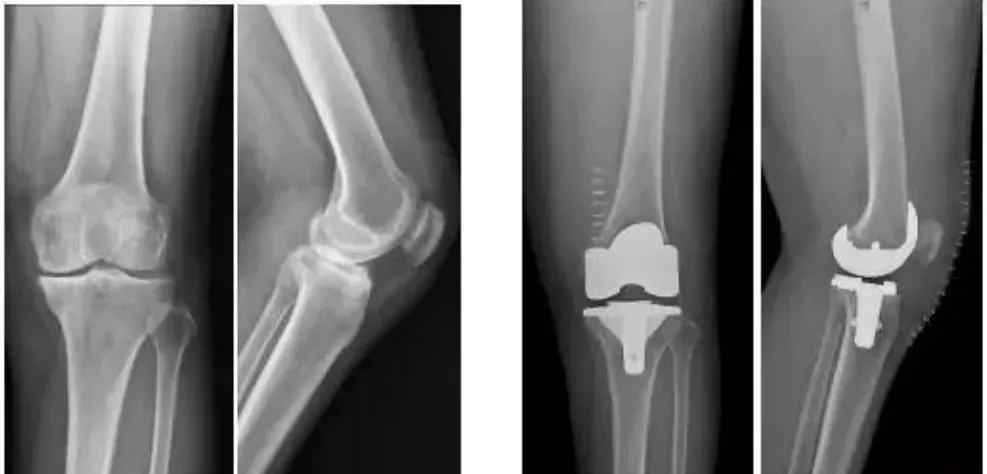

9月30日,四川大學華西醫院骨科的周宗科教授團隊成功為患有膝關節骨關節炎的吳婆婆植入了3D打印分區骨小梁生物型膝關節假體。飽受膝關節疼痛折磨多年的她,在接受手術20多天后,恢復了正常的行走能力。

這種新型假體與傳統骨水泥假體相比,其通過假體—骨界面緊密接觸,促使骨組織長入假體,提高假體與髓腔的結合強度,從而達到假體的長期穩定。使用生物型人工膝關節,可保存患者骨量,同時避免或降低了骨水泥所導致的毒副作用。

640 (2)(1)

圖片版權屬于紅星新聞

全球首款3D打印分區骨小梁生物型膝關節假體

膝關節骨關節炎是一種退行性疾病,近年隨著經濟發展和人口老齡化趨勢日趨明顯,尤其是在中老年群體發病率較高,因此膝關節置換術需求量日益增長。此外,隨著居民生活水平的提高,大多患者對于膝關節置換術術后的生活質量和植入假體有了更高的要求,隨之假體在設計和創新方面也更精準、更便捷化。全球首款3D打印分區骨小梁生物型膝關節假體正是在這種高需求與高期待的新形勢下應運而生。

目前臨床上使用的膝關節假體多為骨水泥固定型假體,骨水泥即骨粘固劑,它可以將膝關節假體固定在骨界面上。骨水泥固定存在一定局限,如骨水泥單體具有一定的毒性;與骨接觸面的骨溶解問題;隨著時間推移,會發生變形和退變等。

本次植入的生物型膝關節假體在術中無需使用骨水泥,通過機械方式進行固定,即假體與骨組織的緊密結合,獲得假體的初始穩定性,遠期骨組織長入假體表面的微孔內部,實現由機械固定向生物內鎖固定的轉化,終經過骨整合作用獲得良好固定,預期能夠獲得更長的假體壽命。

此外,生物型膝關節假體避免了骨水泥相關并發癥的發生,縮短了手術時間,大程度保留了骨組織。因而減輕了患者術后疼痛,降低了圍術期并發癥發生率,有利于患者術后快速康復。

周宗科教授介紹說,該款3D打印分區骨小梁生物型膝關節假體有三個亮點,一是脛骨平臺假體采用了3D打印骨小梁分區技術,三分區設計使宿主骨均勻骨長入,避免因應力分布不均而造成平臺假體松動等問題;二是所用股骨髁假體表面為真空等離子噴涂純鈦涂層,其粗糙的接觸面增加了骨誘導的能力,具有優異的即刻穩定和長期穩定性;三是所用平臺墊為添加維生素E的高交聯超高分子量聚乙烯材質,具有優異的耐磨性能。